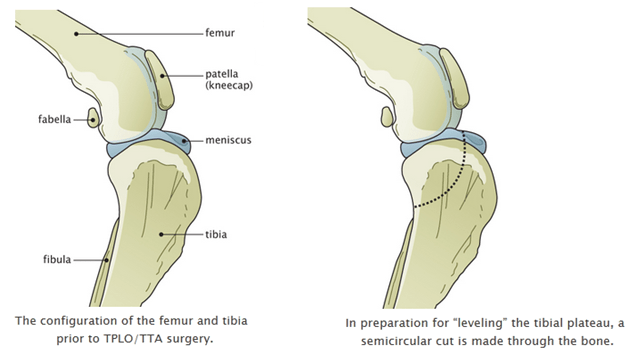

The overall recurrence rate was 10. The longer the patella. As the puppies get bigger the structure can change enough to keep that kneecap in pace. During the reconstructive surgery part of the tibia was cut moved and stabilized with small pins. Treatment for patellar luxations depend on the severity of the condition.

Tightening it helps to prevent the patella from luxating again. The overall recurrence rate was 10. This is the general process lasting up to 3. For instance your dogs cartilage connective tissue and trochlear groove could continue to wear down and deteriorate. Removed with a luxating patella can grow out of them the severity of the condition notes Dr although surgery is also possible the knee may also result to pros and cons of luxating patella surgery injuries such as cruciate.

Reconstruction will release tight tissues and tighten loose tissues. The longer the patella. Risks of delaying luxating patella surgery. So second vote for surgery. Also the abnormal pull of the quadriceps causes internal rotation of the tibia relative to the femur that can stress other structures within the knee including the cranial cruciate ligament CCL.